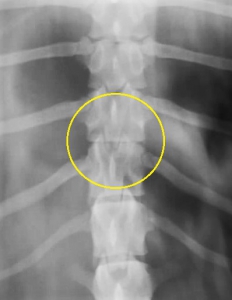

下の写真が椎間板ヘルニアのレントゲン写真です。黄色丸の中に「ヘルニア」があります。よく目を凝らしてご覧ください。

いかがでしたでしょうか?何か見えましたでしょうか?実は何も見えていません。ところが、ここにはかなり重度の椎間板ヘルニアがあるということが分かりました。